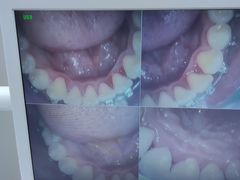

• 牙博士口腔品牌连锁(杨浦店)

• -牙博士口腔品牌连锁(杨浦店)